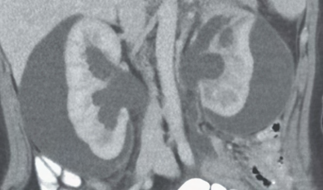

Recent studies indicate that Generative Pre-trained Transformer 4 with Vision (GPT-4V) outperforms human physicians in medical challenge tasks. However, these evaluations primarily focused on the accuracy of multi-choice questions alone. Our study extends the current scope by conducting a comprehensive analysis of GPT-4V's rationales of image comprehension, recall of medical knowledge, and step-by-step multimodal reasoning when solving New England Journal of Medicine (NEJM) Image Challenges - an imaging quiz designed to test the knowledge and diagnostic capabilities of medical professionals. Evaluation results confirmed that GPT-4V outperforms human physicians regarding multi-choice accuracy (88.0% vs. 77.0%, p=0.034). GPT-4V also performs well in cases where physicians incorrectly answer, with over 80% accuracy. However, we discovered that GPT-4V frequently presents flawed rationales in cases where it makes the correct final choices (27.3%), most prominent in image comprehension (21.6%). Regardless of GPT-4V's high accuracy in multi-choice questions, our findings emphasize the necessity for further in-depth evaluations of its rationales before integrating such models into clinical workflows.